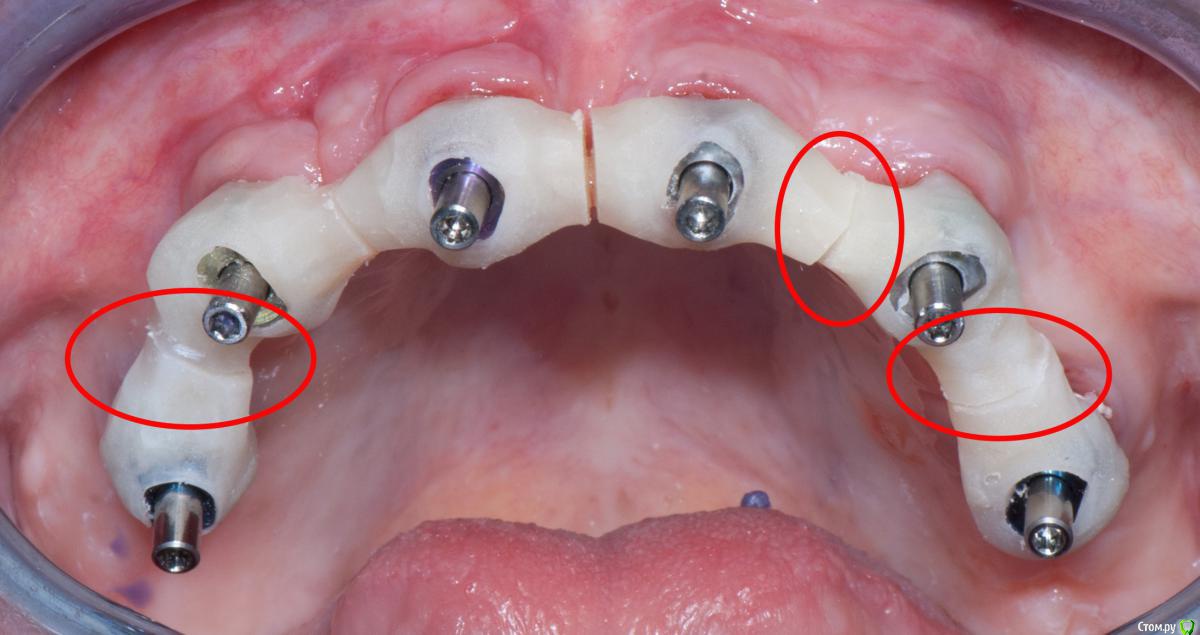

RuStom Опубликовано 25 июня, 2017 Поделиться Опубликовано 25 июня, 2017 (изменено) У Вас Астра, Нобель или что еще? Кто мешает проверить? Вы еще не раз их крутить будете туда-сюда. Внизу Астра, вверху Нобель. Астровские я проверил. И, думаю, что очень зря. Они прямые. 2 из 8 немного докрутились. Не сильно, но всё-таки. Получается, что они стали хоть на микроны, но ниже (глубже). Теоретически временный протез будет сидеть не так идеально...Вверху Нобель, там, думаю, можно проверить. Там угловые и они никуда не просят в случае докрутки... Изменено 25 июня, 2017 пользователем RuStom Ссылка на комментарий

Doc Опубликовано 25 июня, 2017 Поделиться Опубликовано 25 июня, 2017 Внизу Астра, вверху Нобель. Астровские я проверил. И, думаю, что очень зря. Они прямые. 2 из 8 немного докрутились. Не сильно, но всё-таки. Получается, что они стали хоть на микроны, но ниже (глубже). Теоретически временный протез будет сидеть не так идеально...Вверху Нобель, там, думаю, можно проверить. Там угловые и они никуда не просят в случае докрутки...Значит недокрутили при посадке. Первый раз слышу, что через 5 месяцев после времянок они могли раскрутиться. Обычно наоборот, у Астры их крайне сложно открутить. И уж лучше времянка пусть сейчас будет не идеальна, чем потом постоянные. 1 Ссылка на комментарий